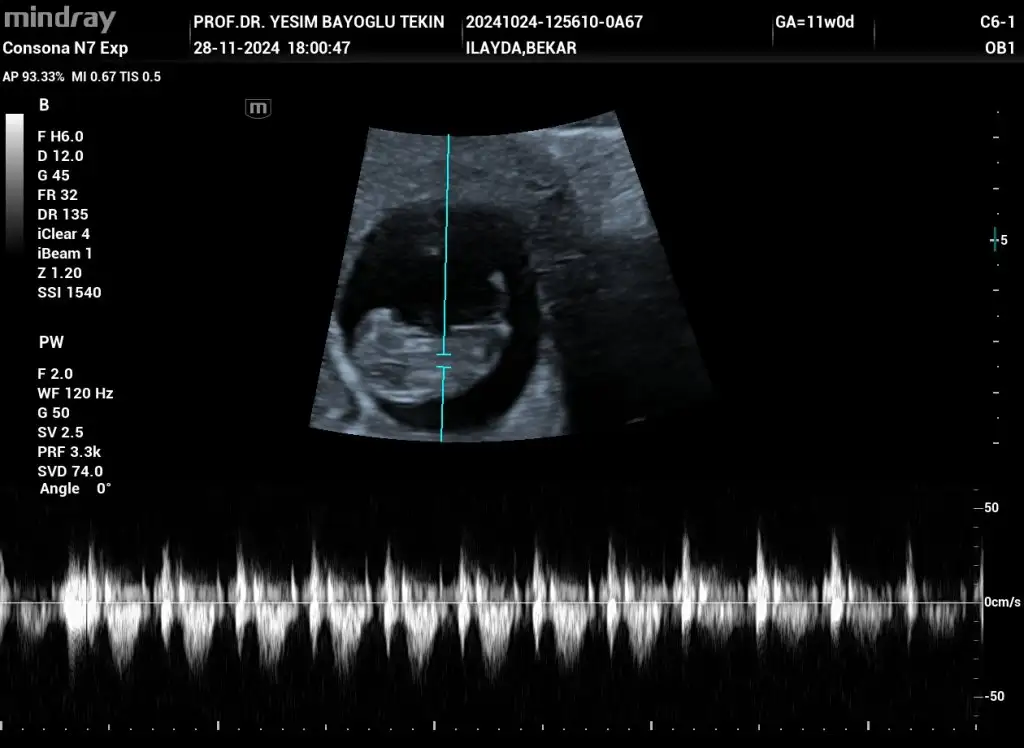

kızlar son kez cinsiyet tahminiiii

Belli değil canım ya haftaya net söyleyeceğim dedi doktorum ☺️ Yeni ultrasonlar var ama atayım bakalım yeni tahminler ne olacak ♥️

Merhaba 10 haftalık cinsiyet tahmini yapabilir misiniz rica etsem